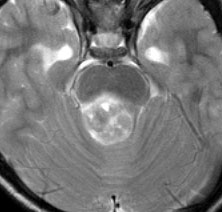

10才の時に,複雑部分発作(症候性てんかん)で発症しました。吐き気を感じた後に嘔吐して意識が遠くなる(意識減損)という症状であり,側頭葉てんかんです。脳波では左側頭葉に徐波律動がみられました。発作は頻回でしたがカルバマゼピンの投与で抑制されていましたが,MRIで腫瘍が発見されました。

左内側側頭葉グリオーマ mesial temporal glioma と呼ばれる腫瘍です。左の扁桃体,海馬鉤,海馬,海馬傍回に腫瘍が浸潤しています。T2強調画像とFLAIRでまだらな高信号で境界ははっきりしません。mass effectが少なく,増殖増大傾向のある腫瘍には見えないのが特徴です。下段右のように部分的にガドリニウム増強されるのも神経節細胞腫の特徴かもしれません。しかし,神経節膠腫,乏突起膠腫,乏突起星細胞腫(グレード2)なども疑われます。

手術中の脳波モニターでは,棘波が上側頭回の後方(ウェルニッケ領域)に存在し,深部電極刺入で海馬近傍にも棘波がみられましたが,もちろん上側頭回や海馬の切除はしませんでした。扁桃体 amygdala と海馬鈎 uncus の腫瘍部分のみを切除して手術を終了しています。海馬と海馬傍回には腫瘍を残しました。上のMRIは,その後6年経過した後のものですが腫瘍は全く同じ大きさです。抗てんかん薬も止めて,発作は全く生じていません。このような腫瘍は,扁桃体と海馬鉤を摘出することで,発作を完全に止めることができることがあります。ですから,最初の手術では,リスクのある余分な脳切除をしません。

大脳皮質に大型の核を有する円形の神経細胞が散在しています。神経細胞間にグリア細胞がありますが腫瘍性増殖を示しません。MIB-1は1%以下でした。血管周囲にリンパ球浸潤があります。